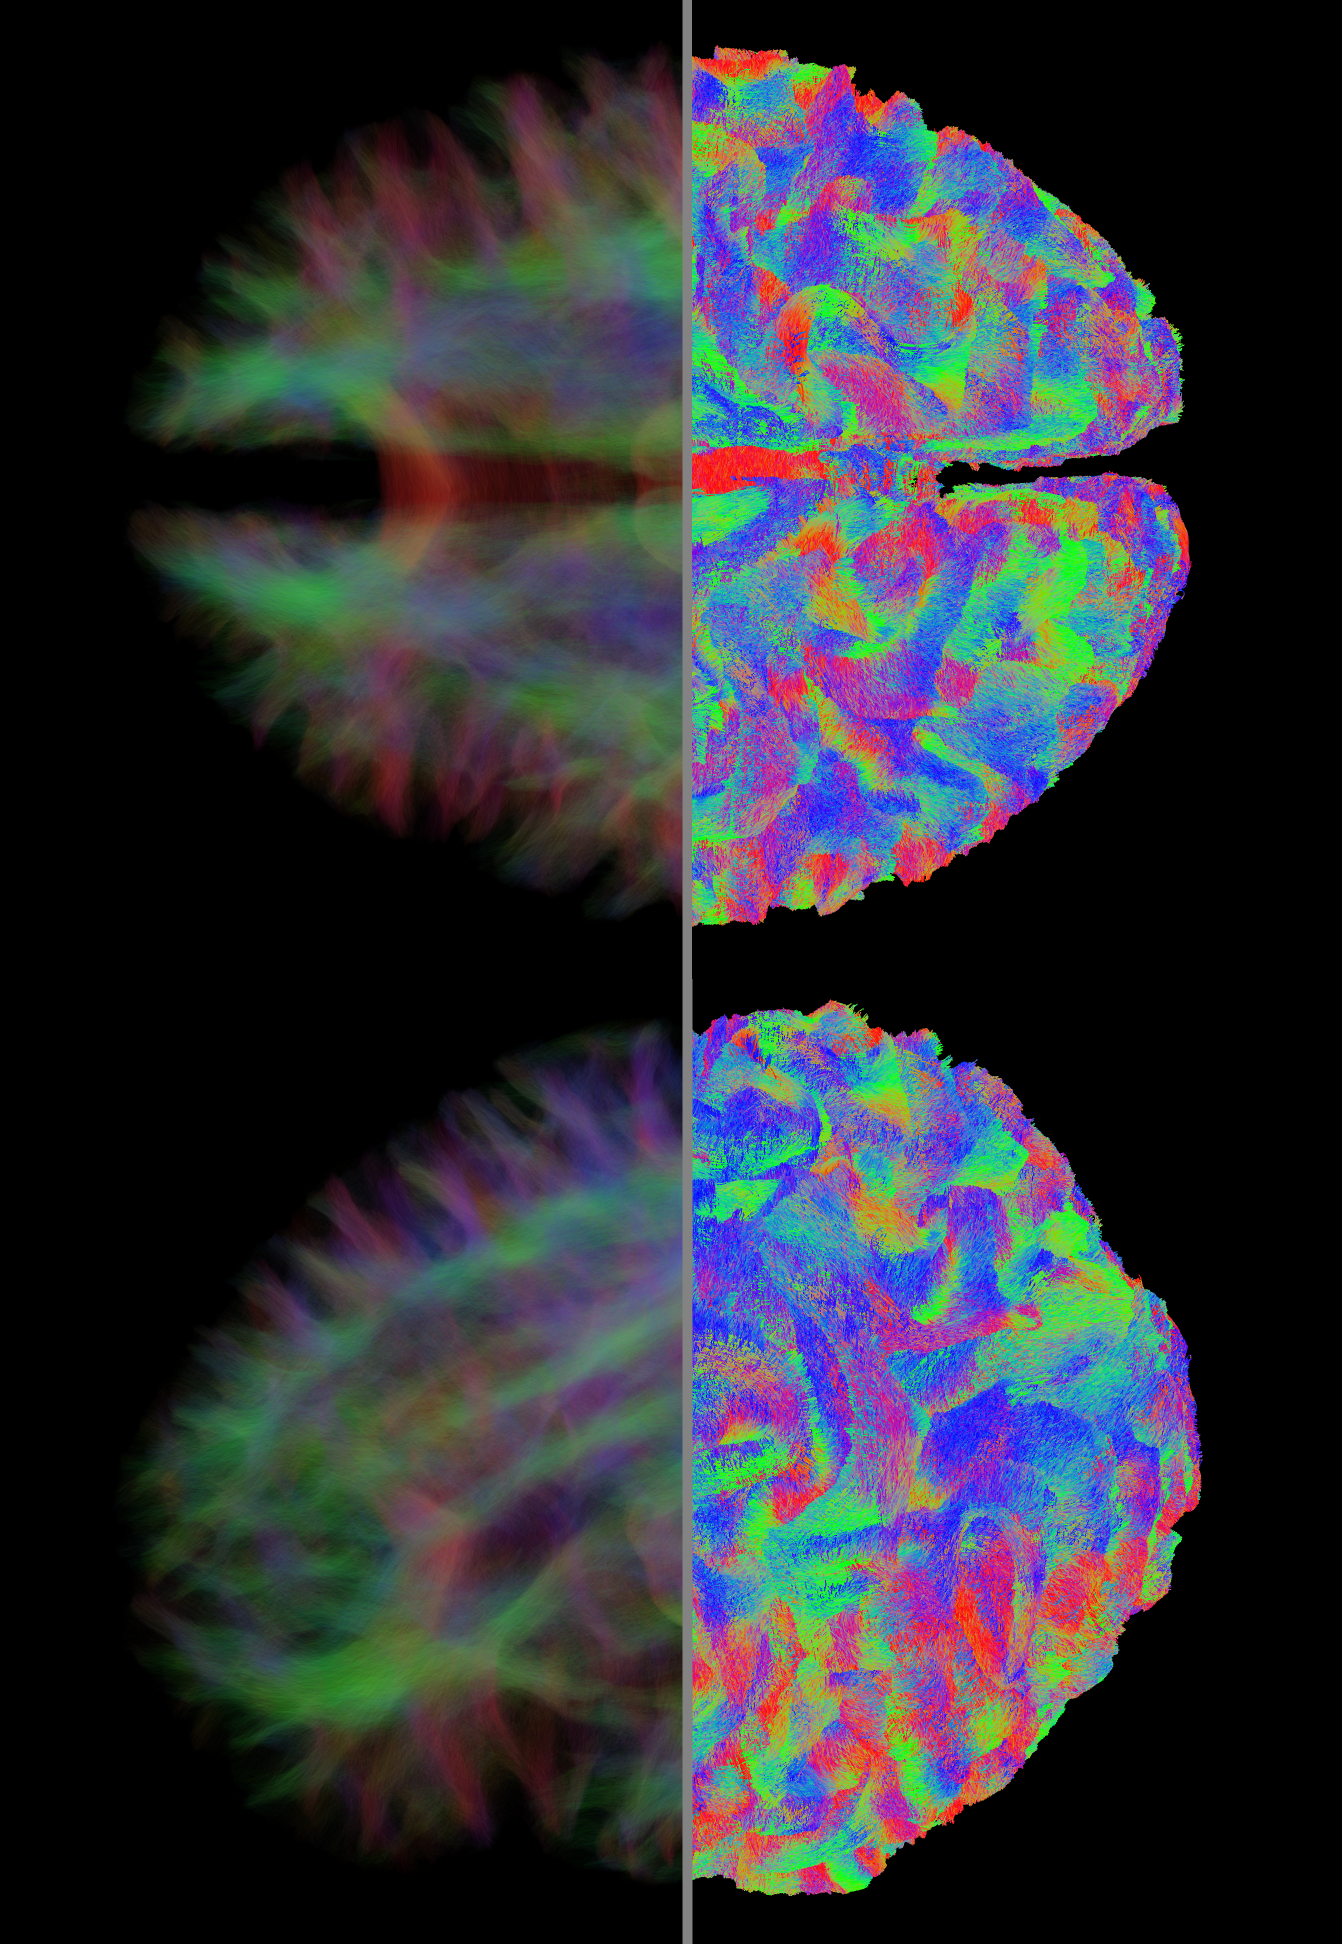

In Figure 4, we demonstrate the difference between axis-based orders and pseudo-random direction orders. We can observe that the axis-based order is more accurate, when the dataset is viewed from one of the sides. Pseudo-random sorting performs worse in these cases. However, when considering arbitrary viewing directions, it outperforms the axis-based approach. Furthermore, when moving the camera, the pseudo-random method exhibits less visual jittering. However, the loading time for the pseudo-random method is worse. In future work, we aim to explore different sorting orders to find a balance between visual quality and performance.